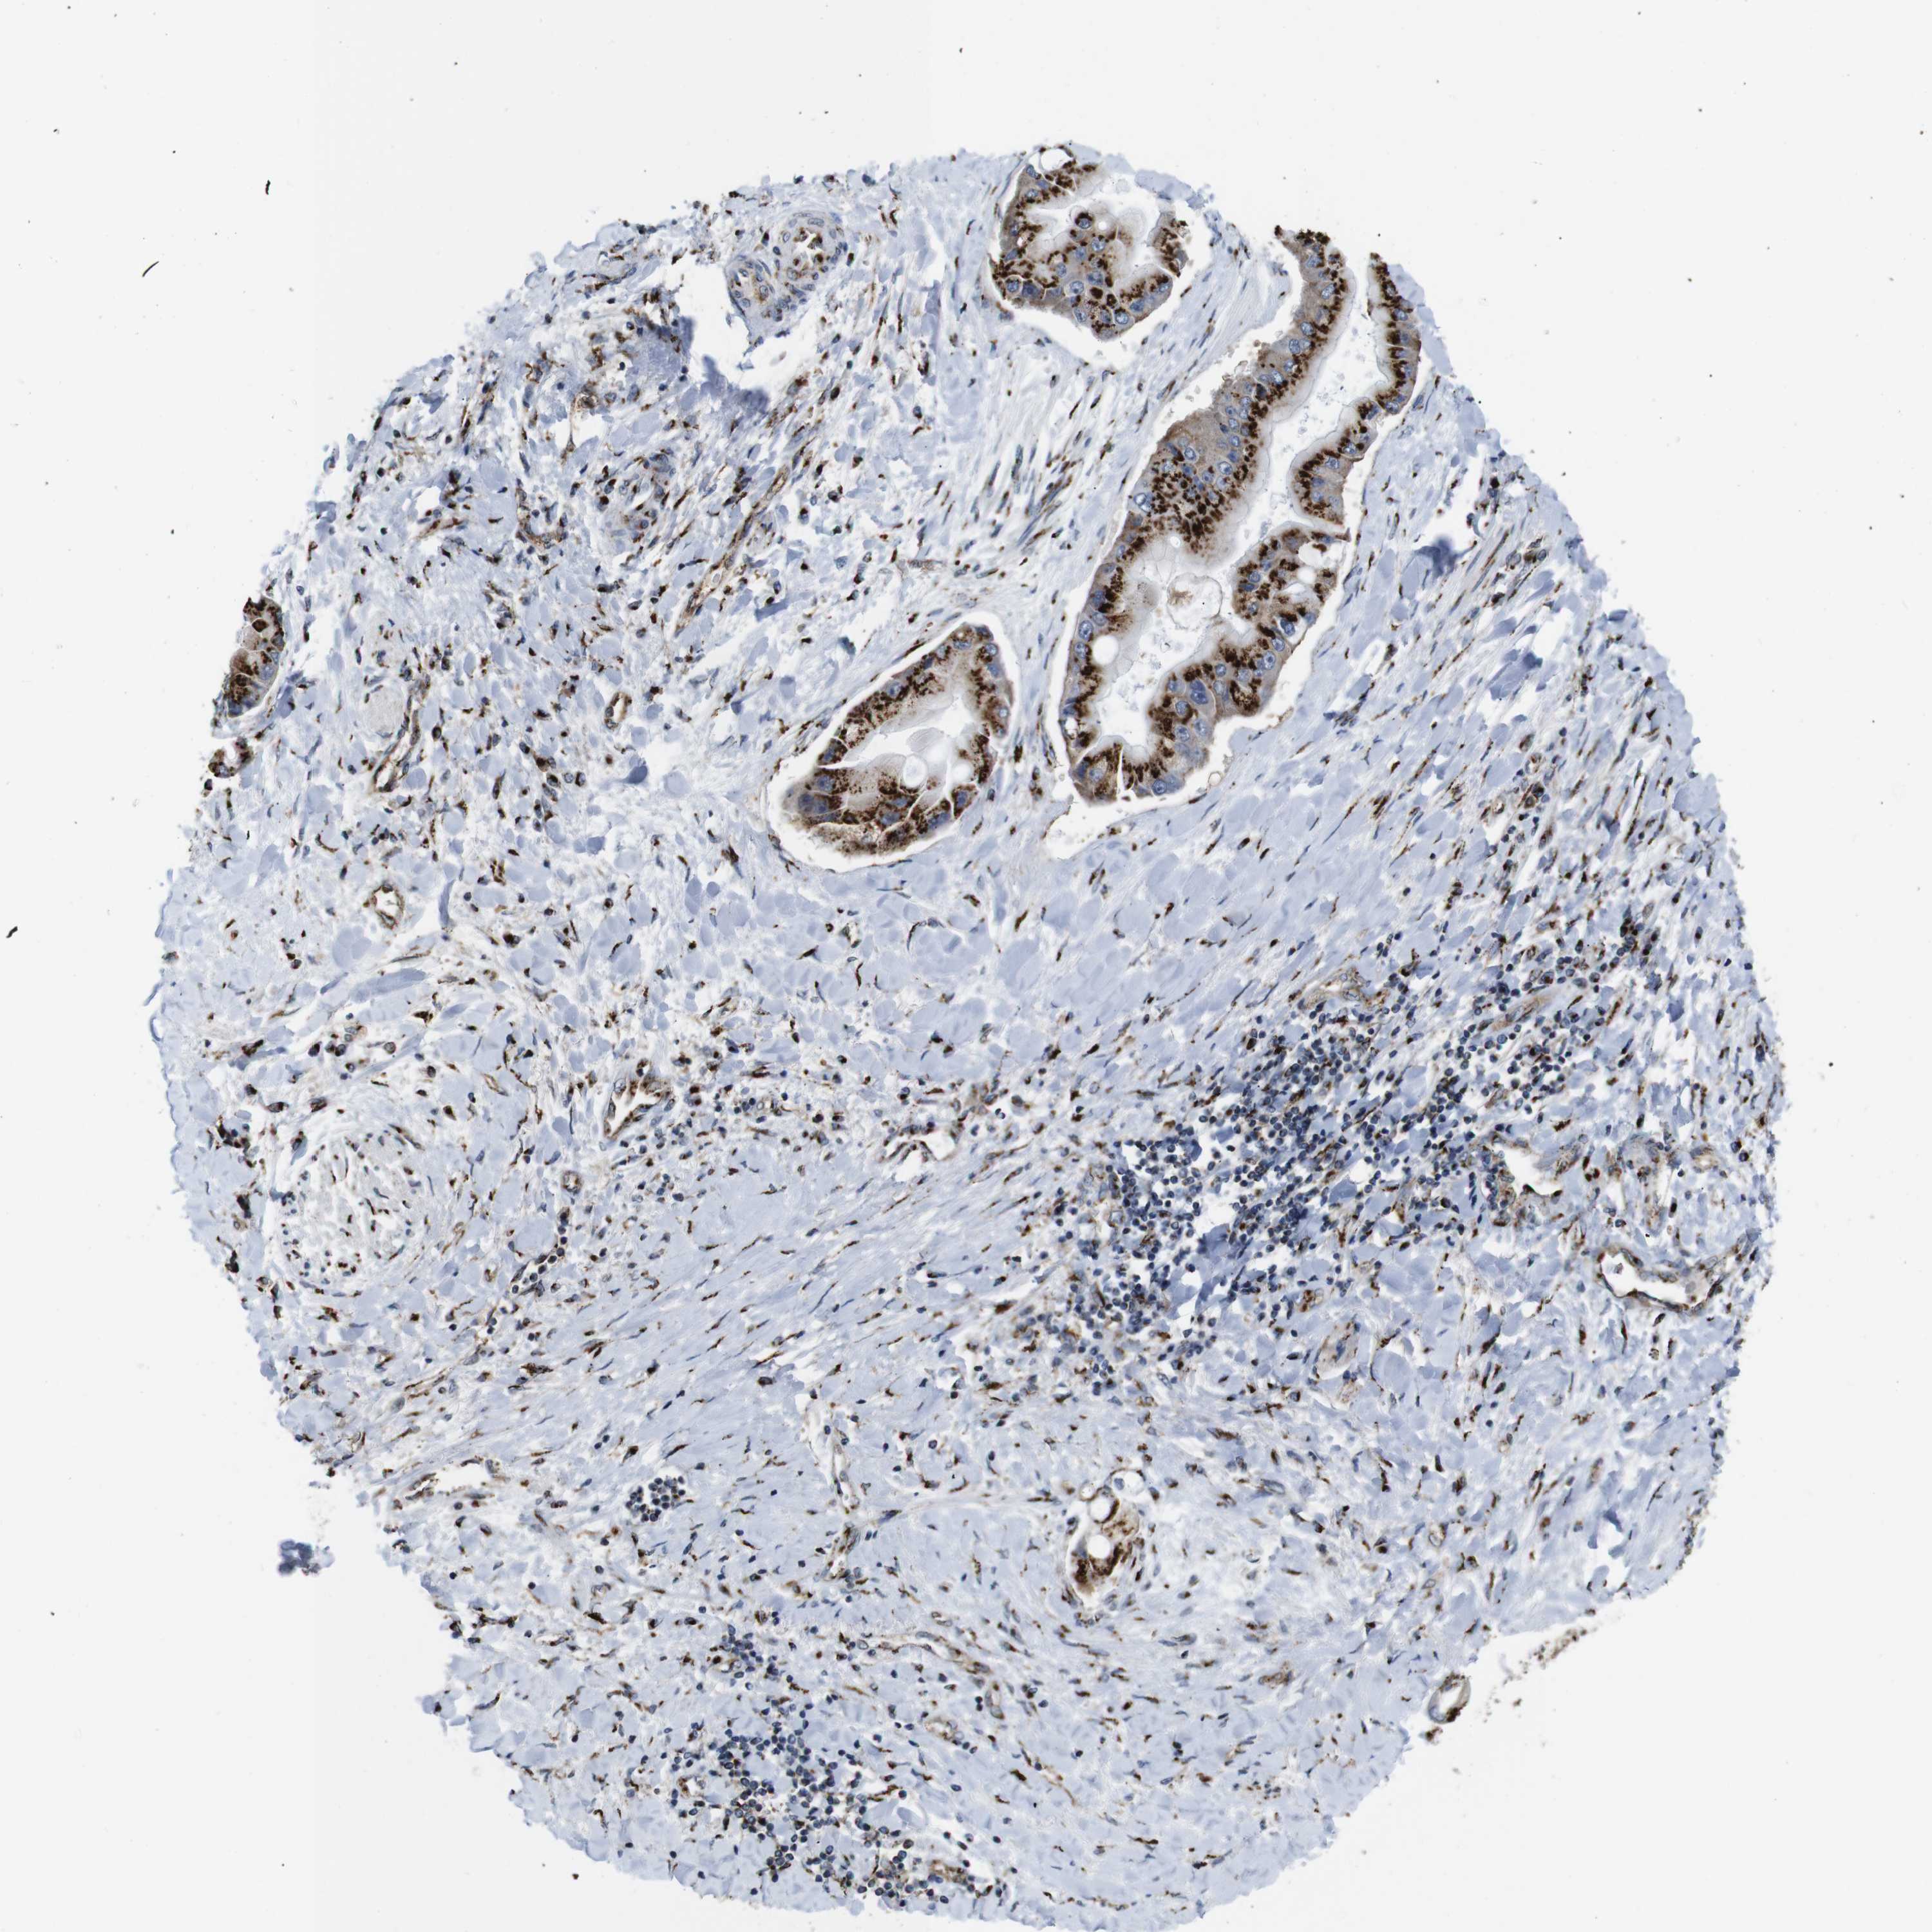

LIVER CANCER - Protein expressioni

A mouse-over function shows sample information and annotation data. Click on an image to view it in a full screen mode. Samples can be filtered based on level of antibody staining by selecting one or several of the following categories: high, medium, low and not detected. The assay and annotation is described here.

Antibody stainingi

Antibody staining in the annotated cell types in the current human tissue is reported as not detected, low, medium, or high, based on conventional immunohistochemistry profiling in selected tissues. This score is based on the combination of the staining intensity and fraction of stained cells.

Each image is clickable and will lead to virtual microscopy that enables deeper exploration of all samples and also displays staining intensity scores, fraction scores and subcellular localization as well as patient and tissue information for each sample.

Antibody HPA012609

Antibody HPA012723

Antibody CAB011489

Staining

High

Medium

Low

Not detected

Intensity

Strong

Moderate

Weak

Negative

Quantity

>75%

75%-25%

<25%

None

Location

Nuclear

Cytoplasmic/membranous

Cytoplasmic/membranous,nuclear

Cholangiocarcinoma

Carcinoma, Hepatocellular, NOS